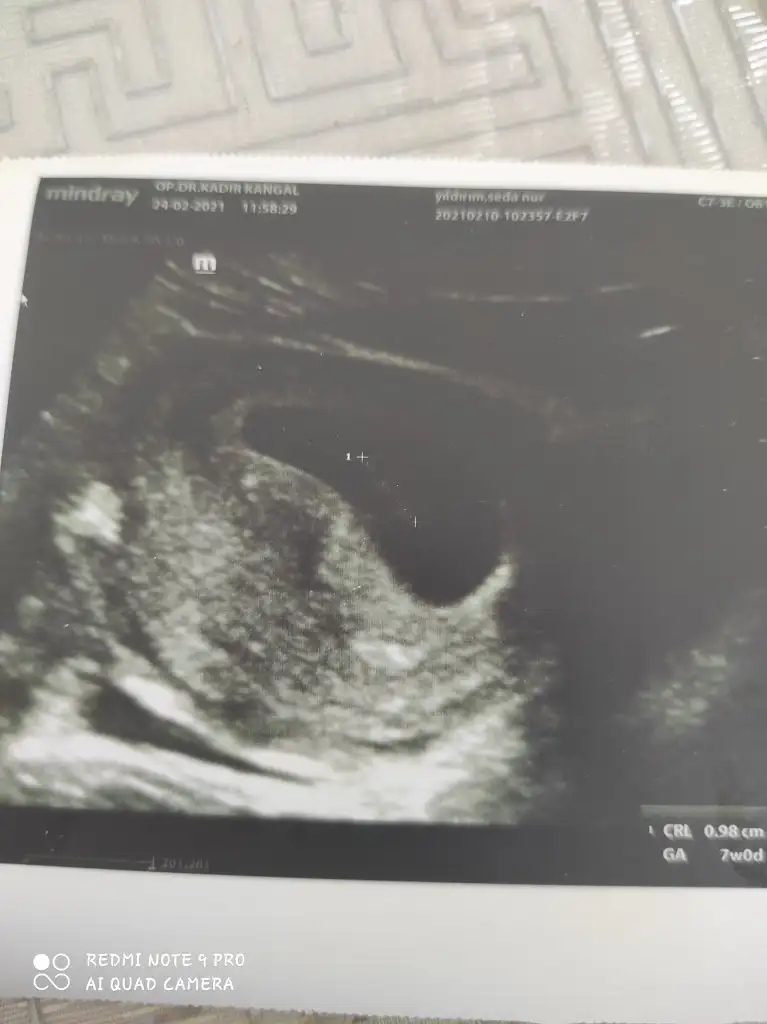

Geldi sonuçlarımız çok şükür iyi görünüyorlar ya bakalım doktorum ne diyecek. İnşallah hepimiz sağ salim kucağımıza alırız yaAllah hayırlara çıkarsın canım. Hiç kötü düşünme zaten bak ultrasonda güzel çıkmış inşallah kan testinde öyle olur Allahın izniyleBende saçma saçma rüyalar gördüm dün gece korktum baya hatta.Tam hamile rüyasıydı yani

![]()